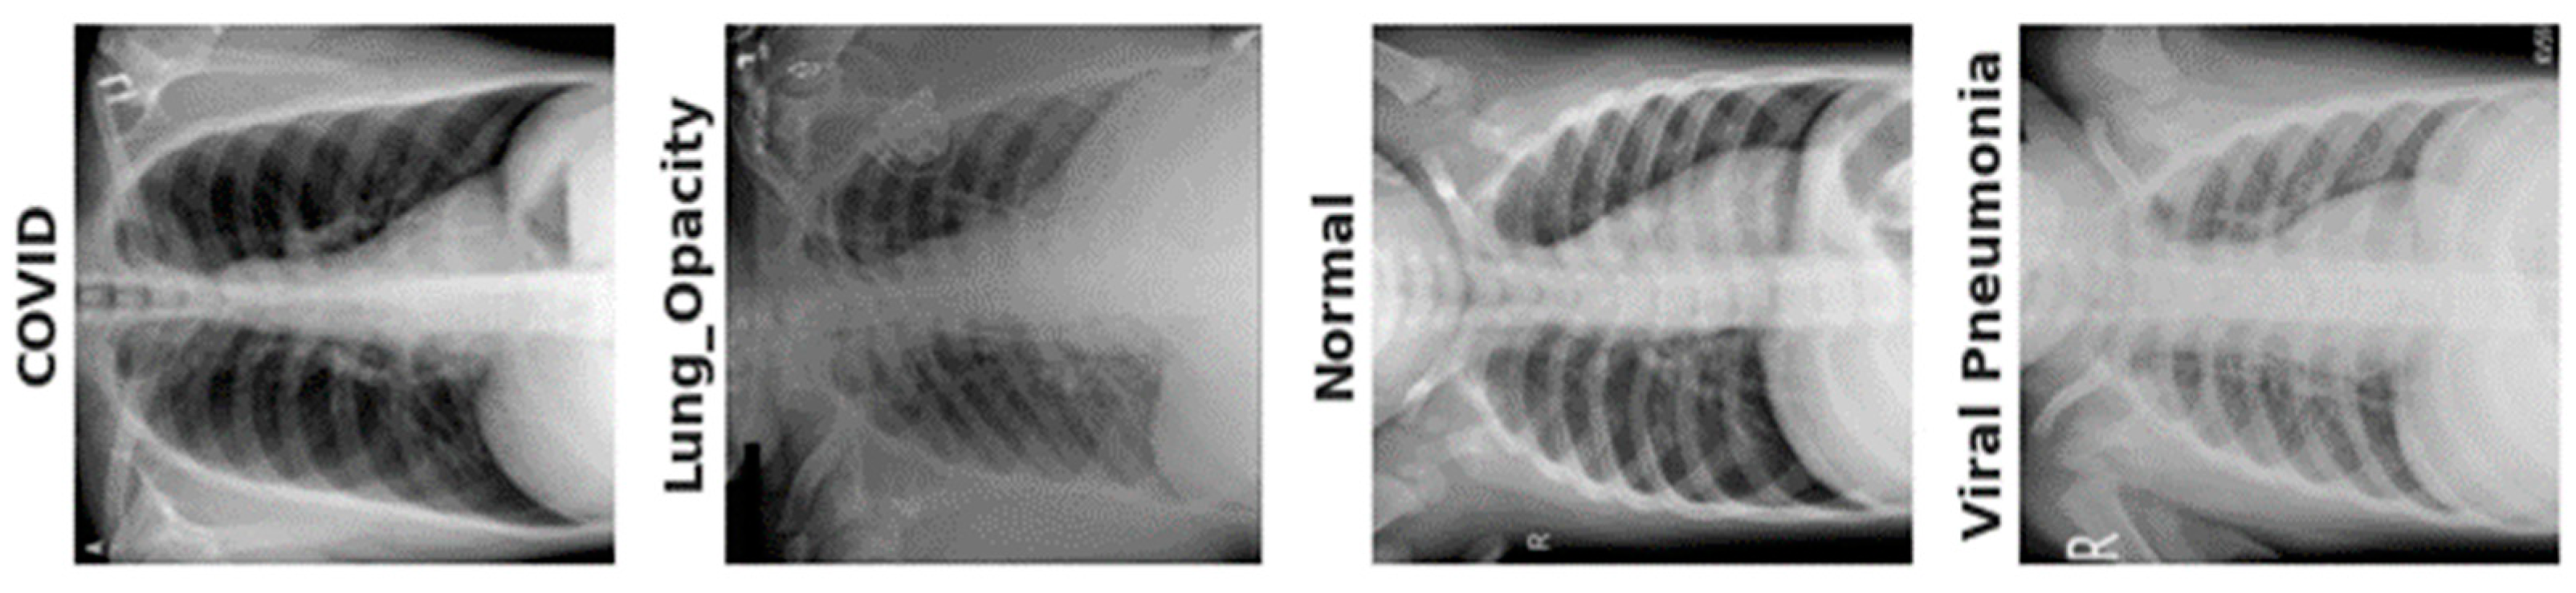

3.1. Data Acquisition

| Step 5: | Prediction = XgBoost classifier is used to classify the images into four classes: lung opacity, COVID-19, pneumonia, and normal |

- The XgBoost classifier was used to predict four-class lung diseases such as COVID-19, viral pneumonia, lung opacity, and normal cases using X-Ray images and a variety of train-test split techniques.